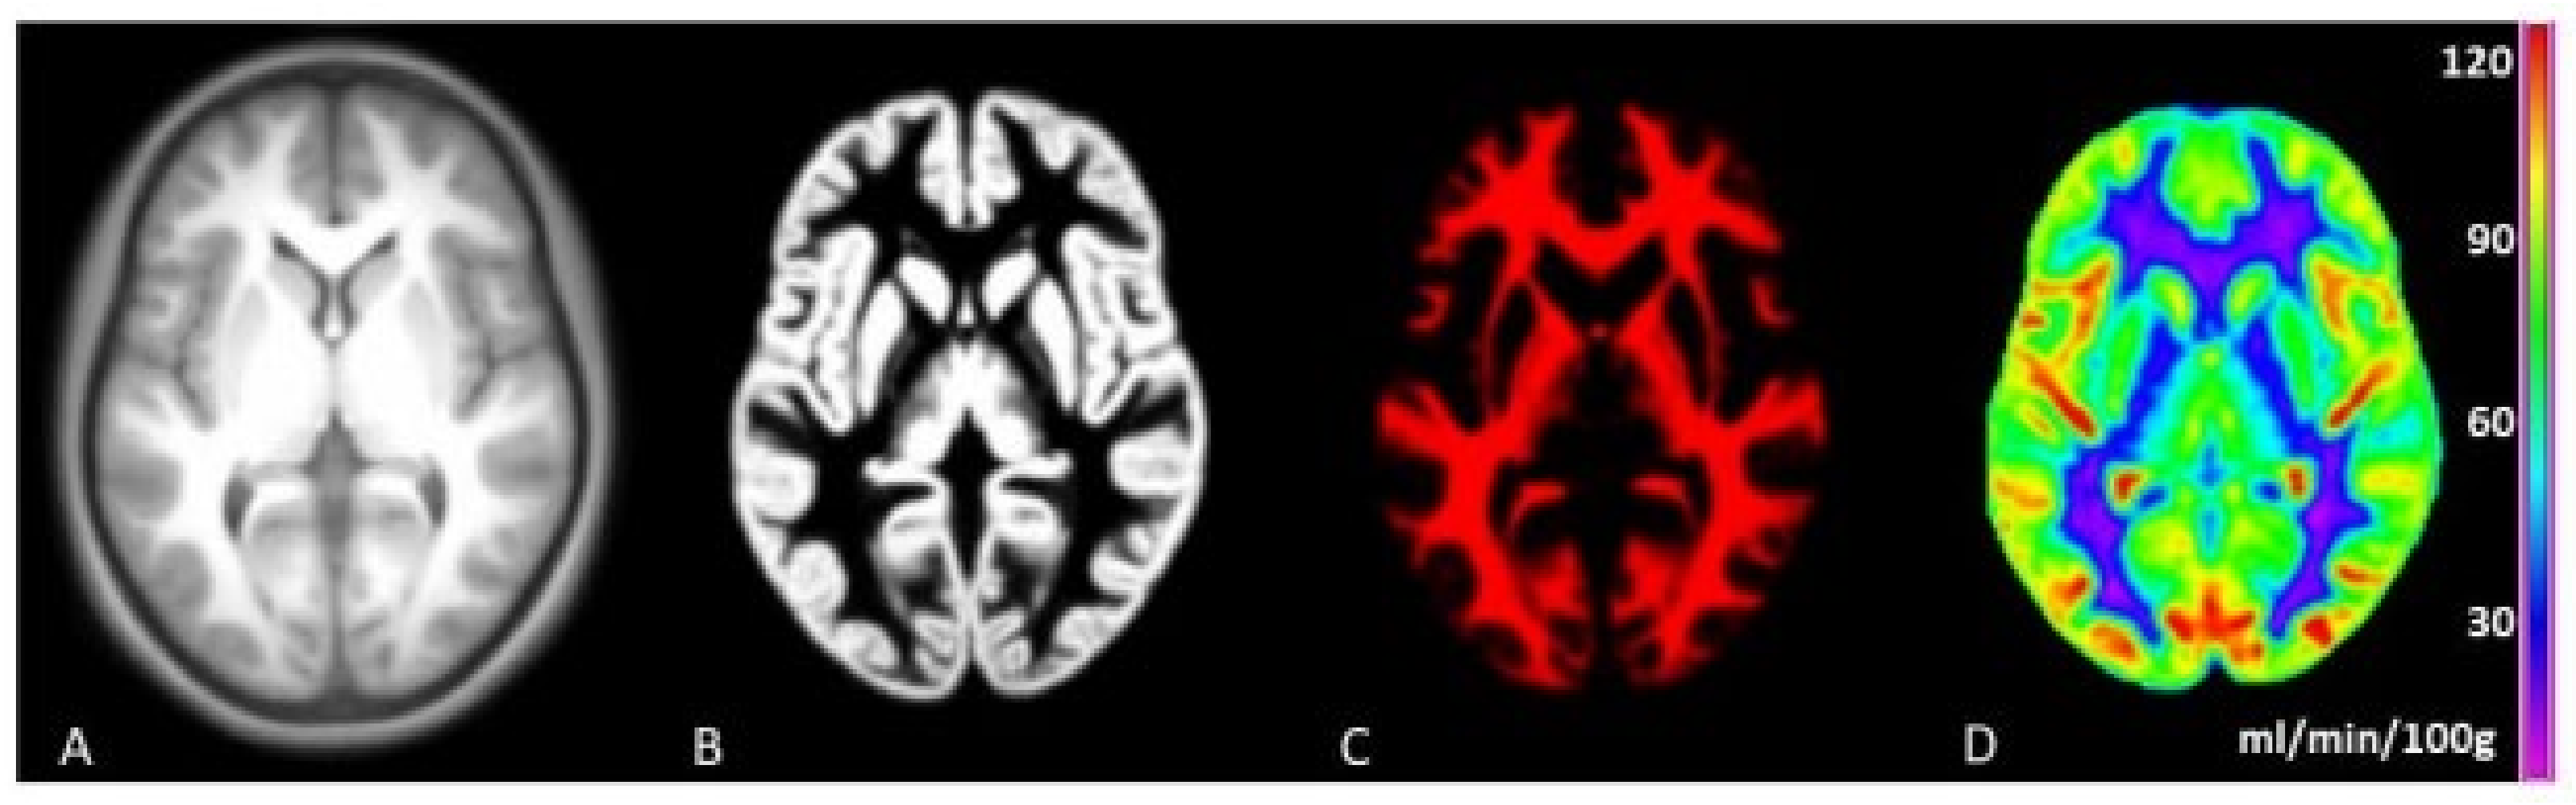

2.2. MRI Data Acquisition

2.3. Image Processing

- Mutsaerts, H.J.M.M.; Petr, J.; Groot, P.; Vandemaele, P.; Ingala, S.; Robertson, A.D.; Václavů, L.; Groote, I.; Kuijf, H.; Zelaya, F.; et al. ExploreASL: An image processing pipeline for multi-center ASL perfusion MRI studies. Neuroimage 2020, 219, 117031. [Google Scholar] [CrossRef]